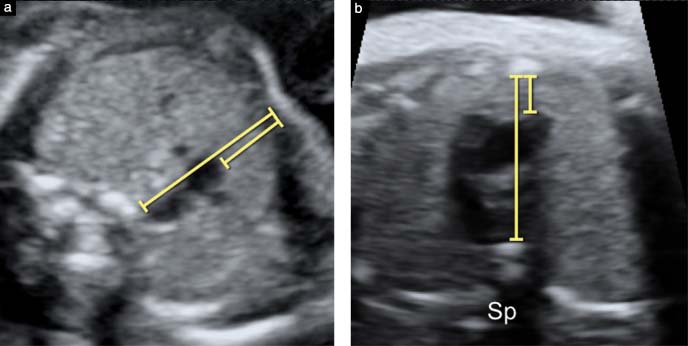

Siêu âm nghi ngờ cũng chưa phải kết luận chắc chắn. Siêu âm phụ thuộc tư thế thai, mặt cắt, và chất lượng hình ảnh. Một cấu trúc có thể trông nhỏ do lệch mặt cắt. Tuyến ức là ví dụ điển hình.

Sai lầm thứ ba là chỉ bám vào một dấu hiệu, như tuyến ức nhỏ. Nhưng 22q11.2 là một phổ. Cần nhìn cả tim, cung động mạch chủ, và các dấu hiệu kèm theo.

Nếu nghi tuyến ức nhỏ, nên kiểm tra lại ở mặt cắt chuẩn. Điều này giúp phân biệt nghi thật và nghi do kỹ thuật. Khám lại sớm giúp bạn có kế hoạch theo mốc thai kỳ. Nó cũng giúp quyết định có cần xét nghiệm chẩn đoán không.